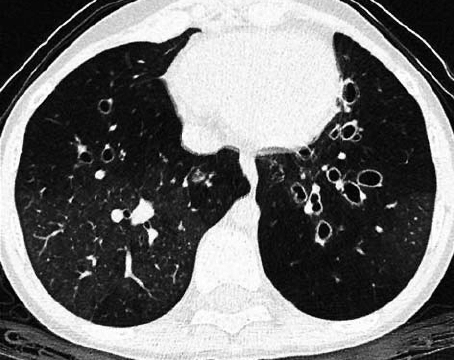

What signs are indicative of bronchiectasis on HRCT in children?

• Bronchial wall thickening

• Diameter of bronchus larger than bronchial artery next to it (Signet Ring)

• Visible peripheral bronchi

Different patterns different aetiologies

• Bilateral upper lobe bronchiectasis commoner in CF

• Unilateral upper lobe bronchiectasis commoner post-TB infection

• Focal bronchiectasis (lower lobe) after foreign body inhalation